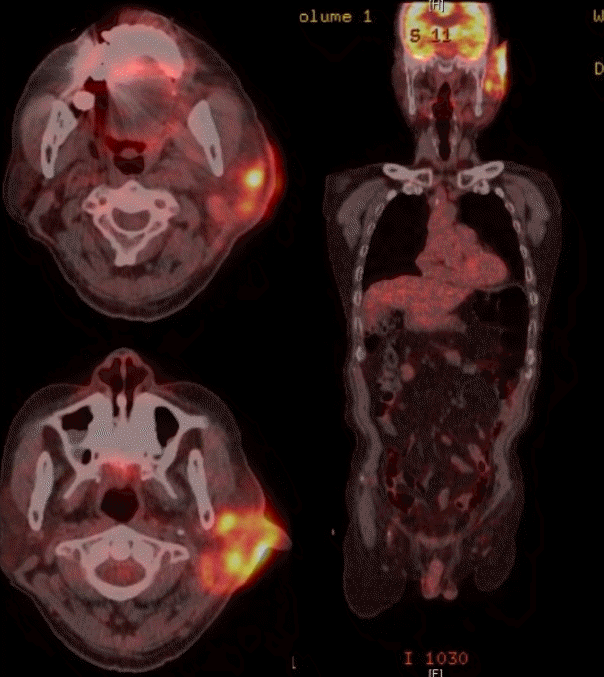

환자 본인의 의사로 타 병원으로 전원 하였고, 본원 최초 내원 두 달 후 타 병원에서 시행한 측두골 자기공명영상에서 좌측 외이도와 이개부 연조직의 부종, 이하선 및 주변 림프절 비대소견으로 염증성 병변과 함께 종양성 상태 의심 소견이 보고되었다(Fig. 4). 재내원 시 병변의 범위는 후이개까지 확장된 악화소견이 관찰되었다(Fig. 2E and F). 환자는 본원에서의 치료 지속을 원하여 양전자컴퓨터단층촬영을 시행하였으며, 좌측 외이도, 이개부 및 이하선을 포함한 불규칙한 과대사성 병변이 관찰되어 악성종양이 여전히 의심되었다(Fig. 5).

PET-CT scan (torso). Left external auditory canal and left ear auricle, periauricular area, left parotid gland involving irregular hypermetabolic lesion was seen.